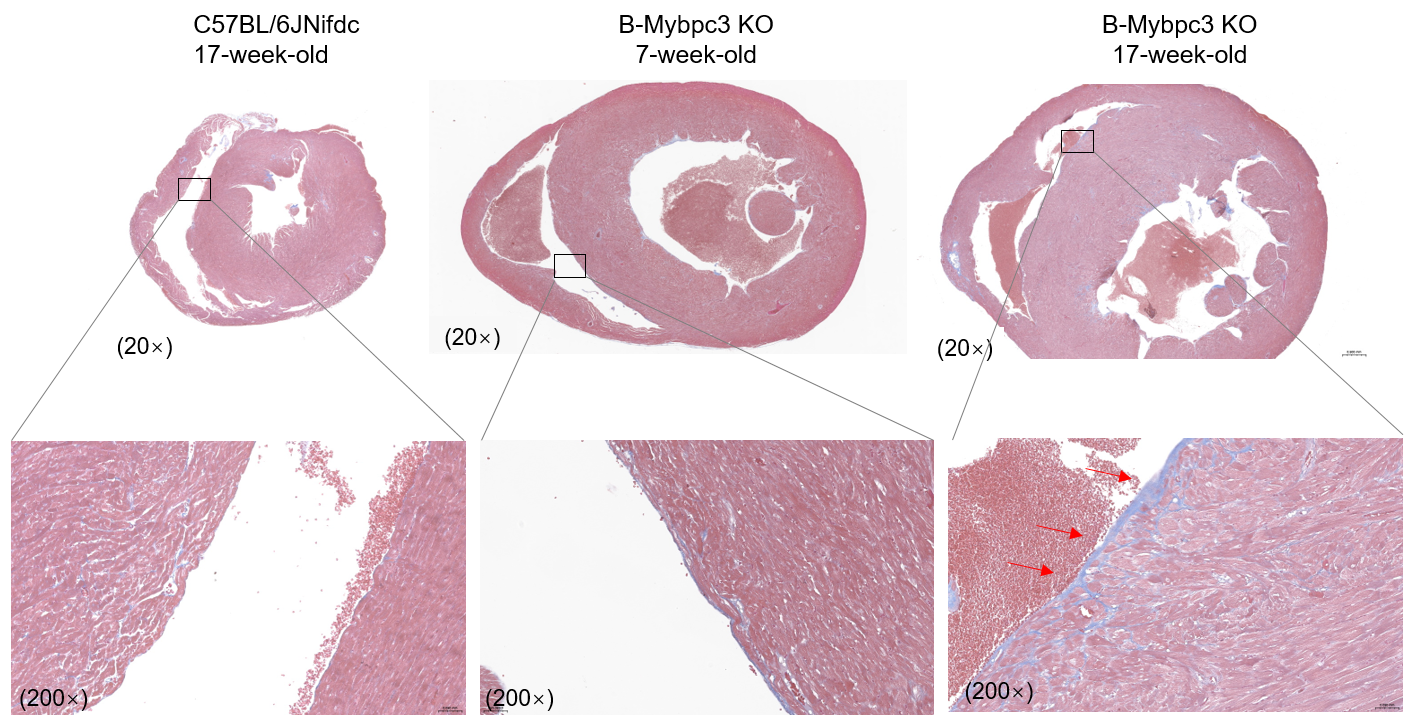

Histopathological analysis of heart tissue in homozygous B-Mybpc3 KO mice. Heart was collected from wild-type C57BL/6JNifdc mice (+/+) (male, 17-week-old, n=2) and homozygous B-Mybpc3 KO mice (-/-) (male, 7-week-old, n=2; male, 17-week-old, n=2), and Masson-staining were performed. Results showed endocardial collagen fiber proliferation in homozygous B-Mybpc3 KO mice (17-week-old) but not in wild-type mice, and the pathological changes in heart tissue are consistent with the characteristics of hypertrophic cardiomyopathy.